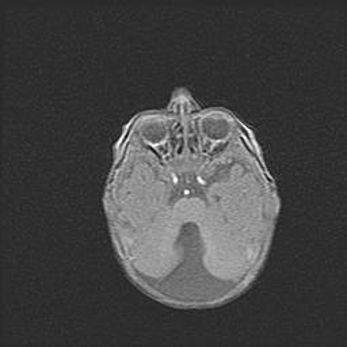

Аномалия Денди-Уокера. Признаки гипоплазии мозолистого тела.

Возраст: 5 месяцев 3 дня

Вес: 5550 г

Пол: мужской

Окружность головы: 39 см

Срок гестации: 40 недель

Аномалия Денди-Уокера – это порок развития головного мозга, для которого характерна триада симптомов: гипотрофия или аплазия червя мозжечка и/или полушарий мозжечка, расширение четвёртого желудочка с формированием ликворной кисты задней черепной ямки, гипертензионная гидроцефалия различной степени.

Гипоплазия мозолистого тела относится к дефектам внутриутробного этапа развития мозговой ткани, возникающим в процессе закладки структур головного мозга, что происходит на начальных этапах развития эмбриона.